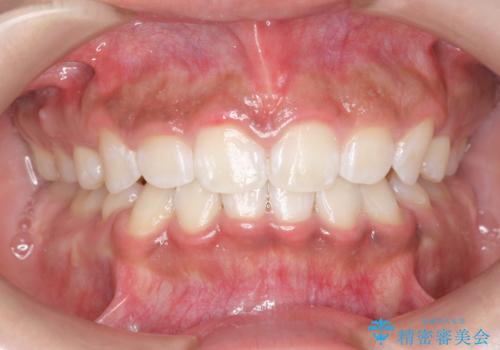

PMTC30分コースを行いました。

全体的に着色がついていました。

歯の面に凹凸があるため、着色が付きやすい患者様です。1-2カ月に1回のペースでクリーニンングを行っています。